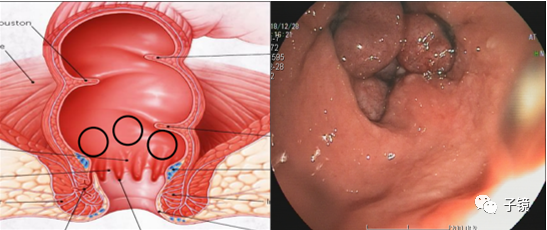

内痔脱垂

套扎环怎么下“中美专家谈内痔内镜下套扎治疗”学习笔记_https://www.jmylbn.com_新闻资讯_第3张

3、分类1)内痔:齿状线以上的静脉扩大曲张和充血形成的柔软静脉团。2)外痔齿状线以下的静脉丛病理性曲张、血栓瘀滞,或反复发炎导致3)混合痔:是内痔通过静脉丛与相应外痔融合,即上、下静脉丛吻合,混合痔脱出肛门外,呈梅花状时,称为环形痔,若被括约肌嵌顿,形成嵌顿性痔。